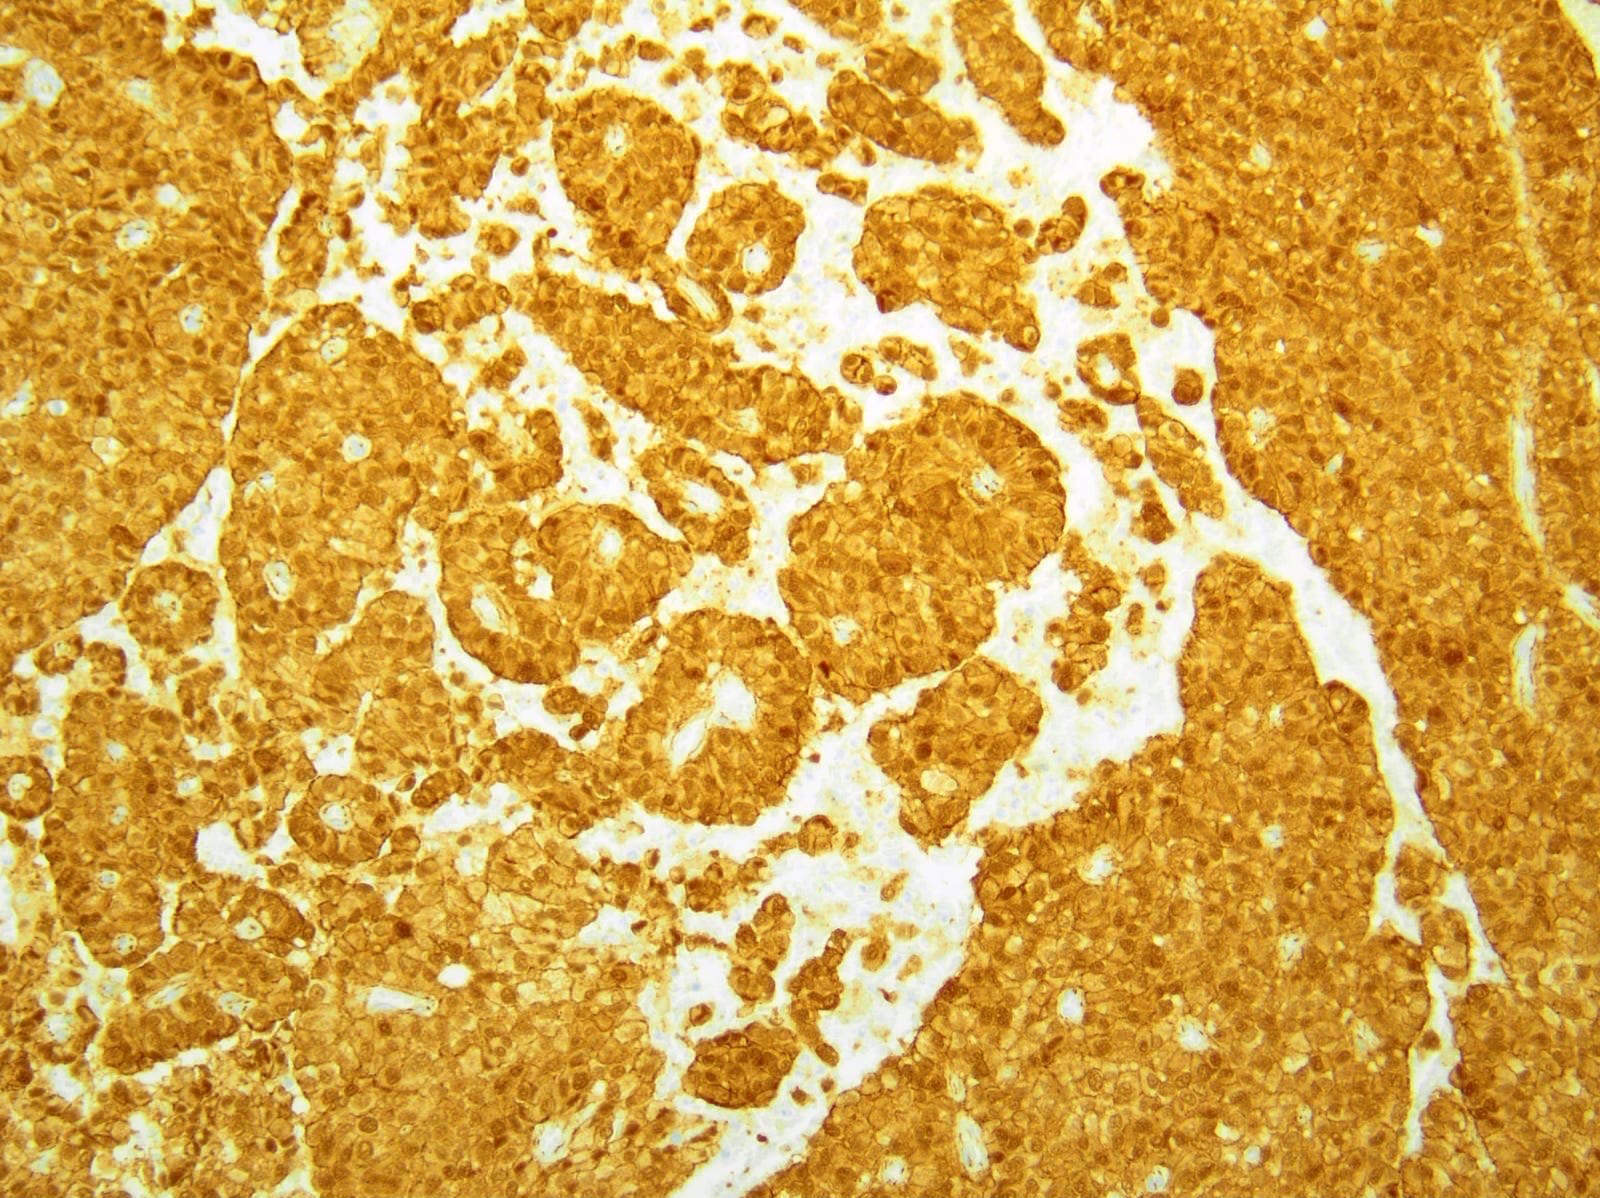

Positive stains

- Beta catenin (98%): aberrant nuclear expression

- E-cadherin (loss of membranous expression) (Hum Pathol 2008;39:251)

- p120 (cytoplasmic staining with loss / reduction of membranous expression) (Am J Clin Pathol 2008;130:71)

- Alpha-1-antichymotrypsin (95%), alpha-1-antitrypsin (82%)

- Vimentin (88%)

- Cyclin D1

- CD10 (63%)

- SOX11 (100%)

- Androgen receptor (81%), TFE3 (75%), LEF1 (93%), FUS (85%), progesterone receptor (63%), claudin7, claudin5 (Am J Surg Pathol 2009;33:768)

- CD56 (96%), neuron specific enolase (70%), synaptophysin (55%)

- Cytokeratin (52%)

- CD99 (dot-like) (Am J Surg Pathol 2011;35:799)

Negative stains

- Chromogranin A (positive in only 9%)

- CEA

- Estrogen receptor

- Reference: Arch Pathol Lab Med 2017;141:990

- Comment: Immunohistochemical stains show the neoplastic cells are positive for CD10 and exhibit nuclear expression of beta catenin while negative for synaptophysin and chromogranin.

- Comment: By immunohistochemistry, the neoplastic cells are positive for CD56, pancytokeratin (focal) and show rare focal positivity for synaptophysin while being negative for chromogranin. Aberrant nuclear expression of beta catenin is present. The histologic and immunohistochemical findings are in keeping with a solid pseudopapillary neoplasm.